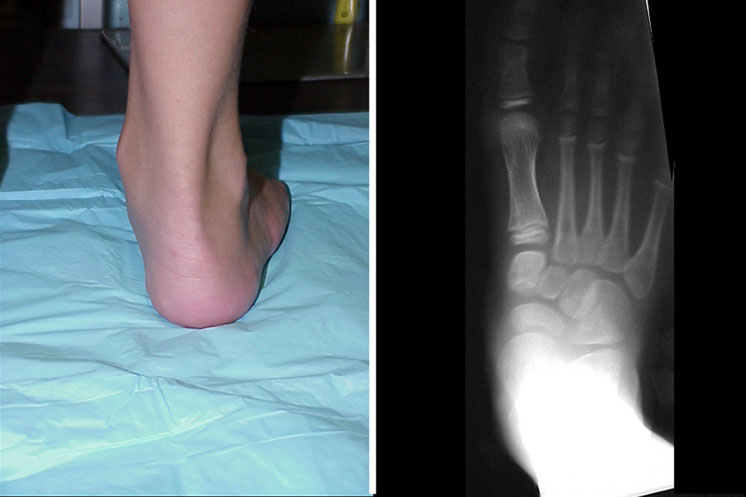

The physical examination shows a plantigrade foot structure when the patient stands. There is moderate prominence of the talar head medially.

In regard to the patient’s subtalar range of motion, there are 30 degrees of inversion and 10 degrees of eversion bilaterally. When the heel is in a vertical position, there are 7 degrees of fixed forefoot varus and the talar head is no longer prominent. Tibial torsion is 20 degrees external on the right and 15 degrees external on the left. When he stands, there is significant genu valgum with 6 inches of malleolar separation when the knees touch. Hip and knee examination are normal, and the patient is neurologically intact.

Standing AP radiographs show the AP talocalcaneal angle is preserved. The lateral radiograph shows marked medial column collapse.

Presumably, the patient is fully pronated in stance and gait. Pain is limited to the talonavicular, calcaneocuboid and sinus tarsi areas. The therapeutic goals are control of the excess pronation and accommodation of the forefoot varus. The deformity dominates in the sagittal plane. Its rigidity limits orthotic therapy to support. One can try a partially pronated device with accommodation for part of the forefoot varus. Physicians should also consider surgical options.